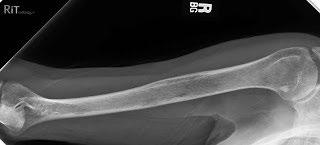

Testing For Myeloma: Imaging

Imaging:

– Skeletal survey: Series of X-rays; less sensitive than other techniques

Healthy bone versus myeloma bone disease

– Whole body low dose (CTWB-LD CT )

– Positron Emission Tomography (PET/CT)

– Magnetic Resonance Imaging (MRI)